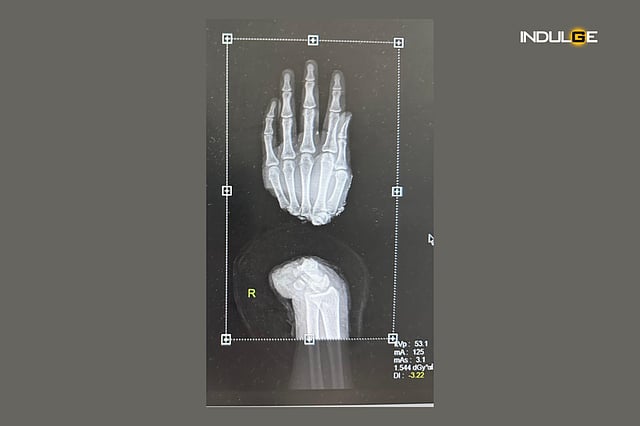

In yet another medical marvel, doctors here have restored the right hand of a 28-year-old daily wage labourer who lost his limb to an accident.

Delhi-based Ashok faced a terrible accident at his work site in Bawana on April 7. As a result, his right hand became completely detached.

The team of doctors at Sir Ganga Ram Hospital in a complex eight-hour surgery worked swiftly to reunite the broken bones, tendons, nerves, arteries, and veins that had been cut during the accident.

"It took us eight hours to completely reattach his right hand, and the patient was discharged after 5 days of monitoring with the hand doing good, and the patient in a stable condition," Nikhil said.